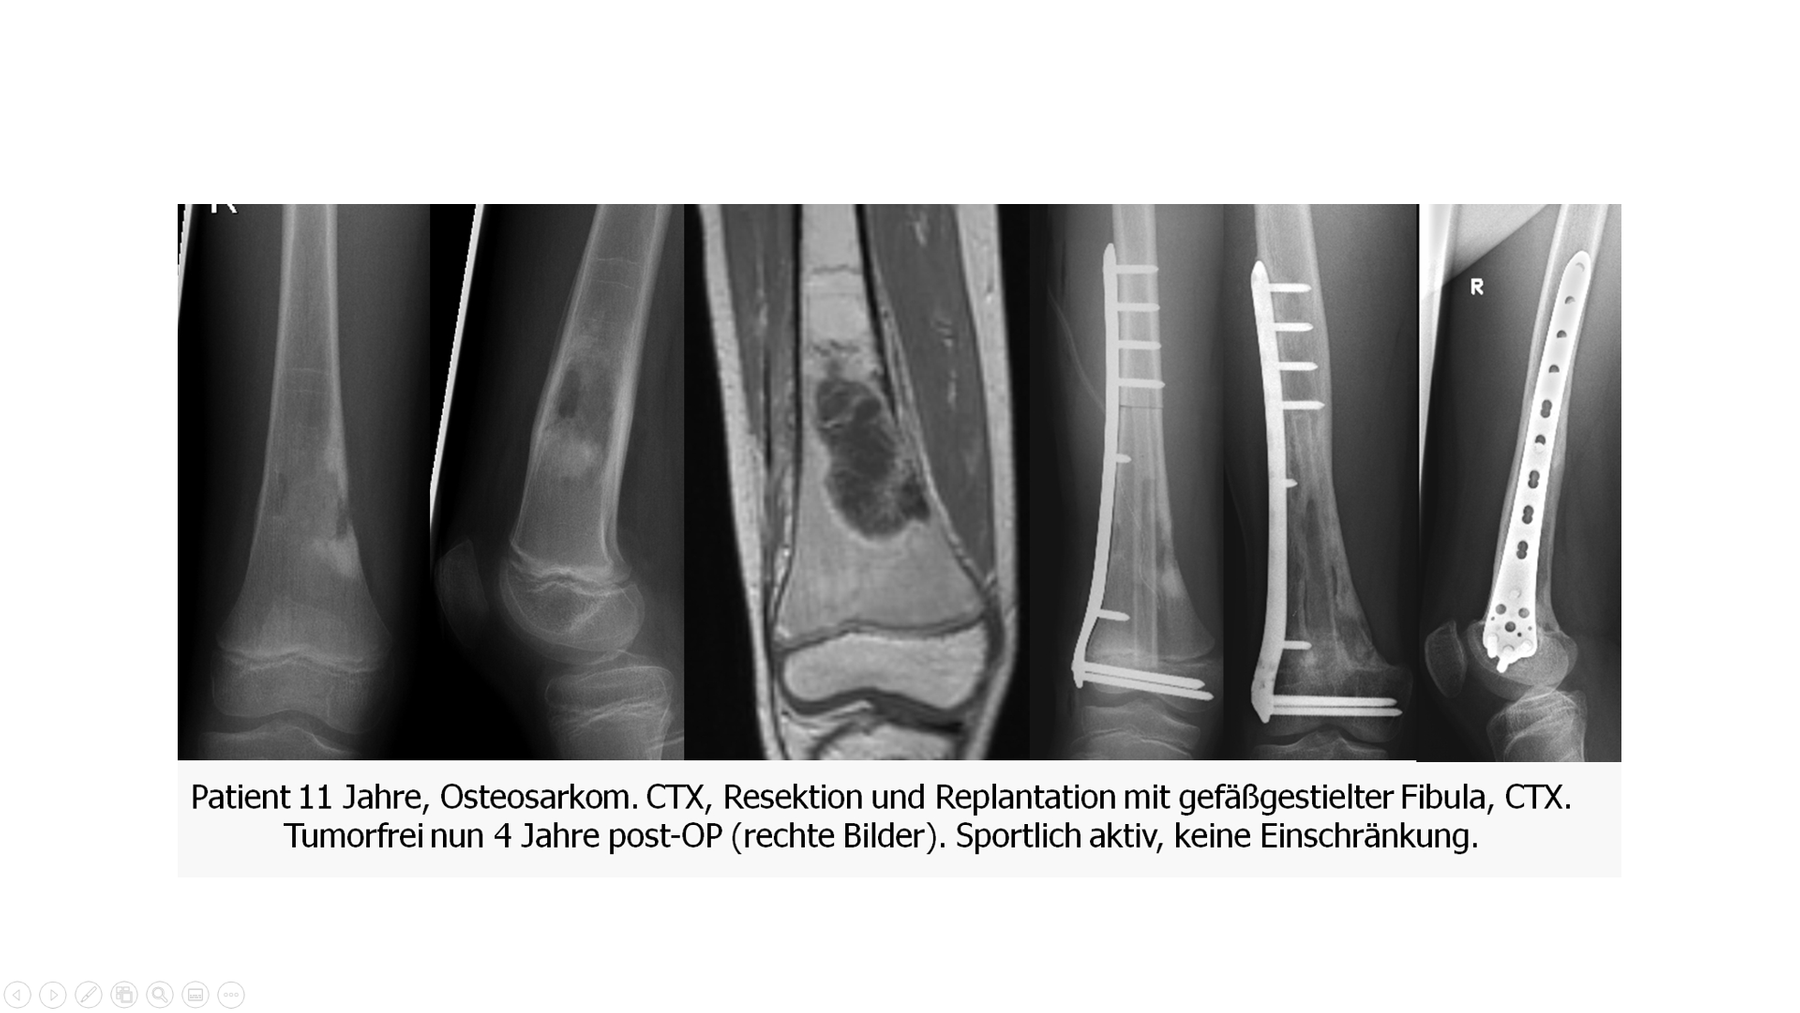

Basierend auf Arbeiten von Manfrini aus Bologna sind dies Kombinationen aus Allografts (oder sterilisierten Autografts als Replantation) und einen gefäßgestielten Fibulatransplantat. Das Allograft wird ausgehölt oder geschlitzt und um das Fibulatransplantat "wie ein Mantel" gelegt. Der Vorteil der Kombination liegt auf der Hand. Anfänglich übernimmt das noch stabile Allograft die Last, die vergleichsweise dünne Fibula wäre hierzu noch nicht in der Lage. Im Laufe der Zeit wird das Allograft zunehmend resorbiert, die autologe Fibula ist jetzt aber eingeheilt und belastbar. Sie nimmt deutlich an Dicke zu. Nachteile sind die komplexe Rekonstruktionsmethode sowie das relativ große Volumen des Gesamttransplantates (mit Osteosynthese). Manchmal kann dies lokal zu Weichteilproblemen führen. In selektierten Fällen ist das Verfahren jedoch eine ausgezeichnete Kombination aus zwei verschiedenen Methoden, die sich ideal ergänzen.